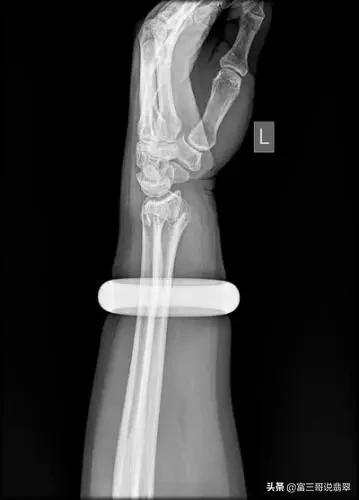

翡翠手镯的圈口是固定的,所以在选择玉镯的时候,圈口是一个非常重要的因素,圈口大了容易脱落,试戴上之后容易摔坏,而圈口小了,硬挤进去,轻则取出时手被挤肿了,重则根本取不出来,无论多贵只能买走,甚至之前还出现过试戴手镯导致手骨变形的事件,让人感叹女人在面对心仪的珠宝时候真的很容易失去理智。